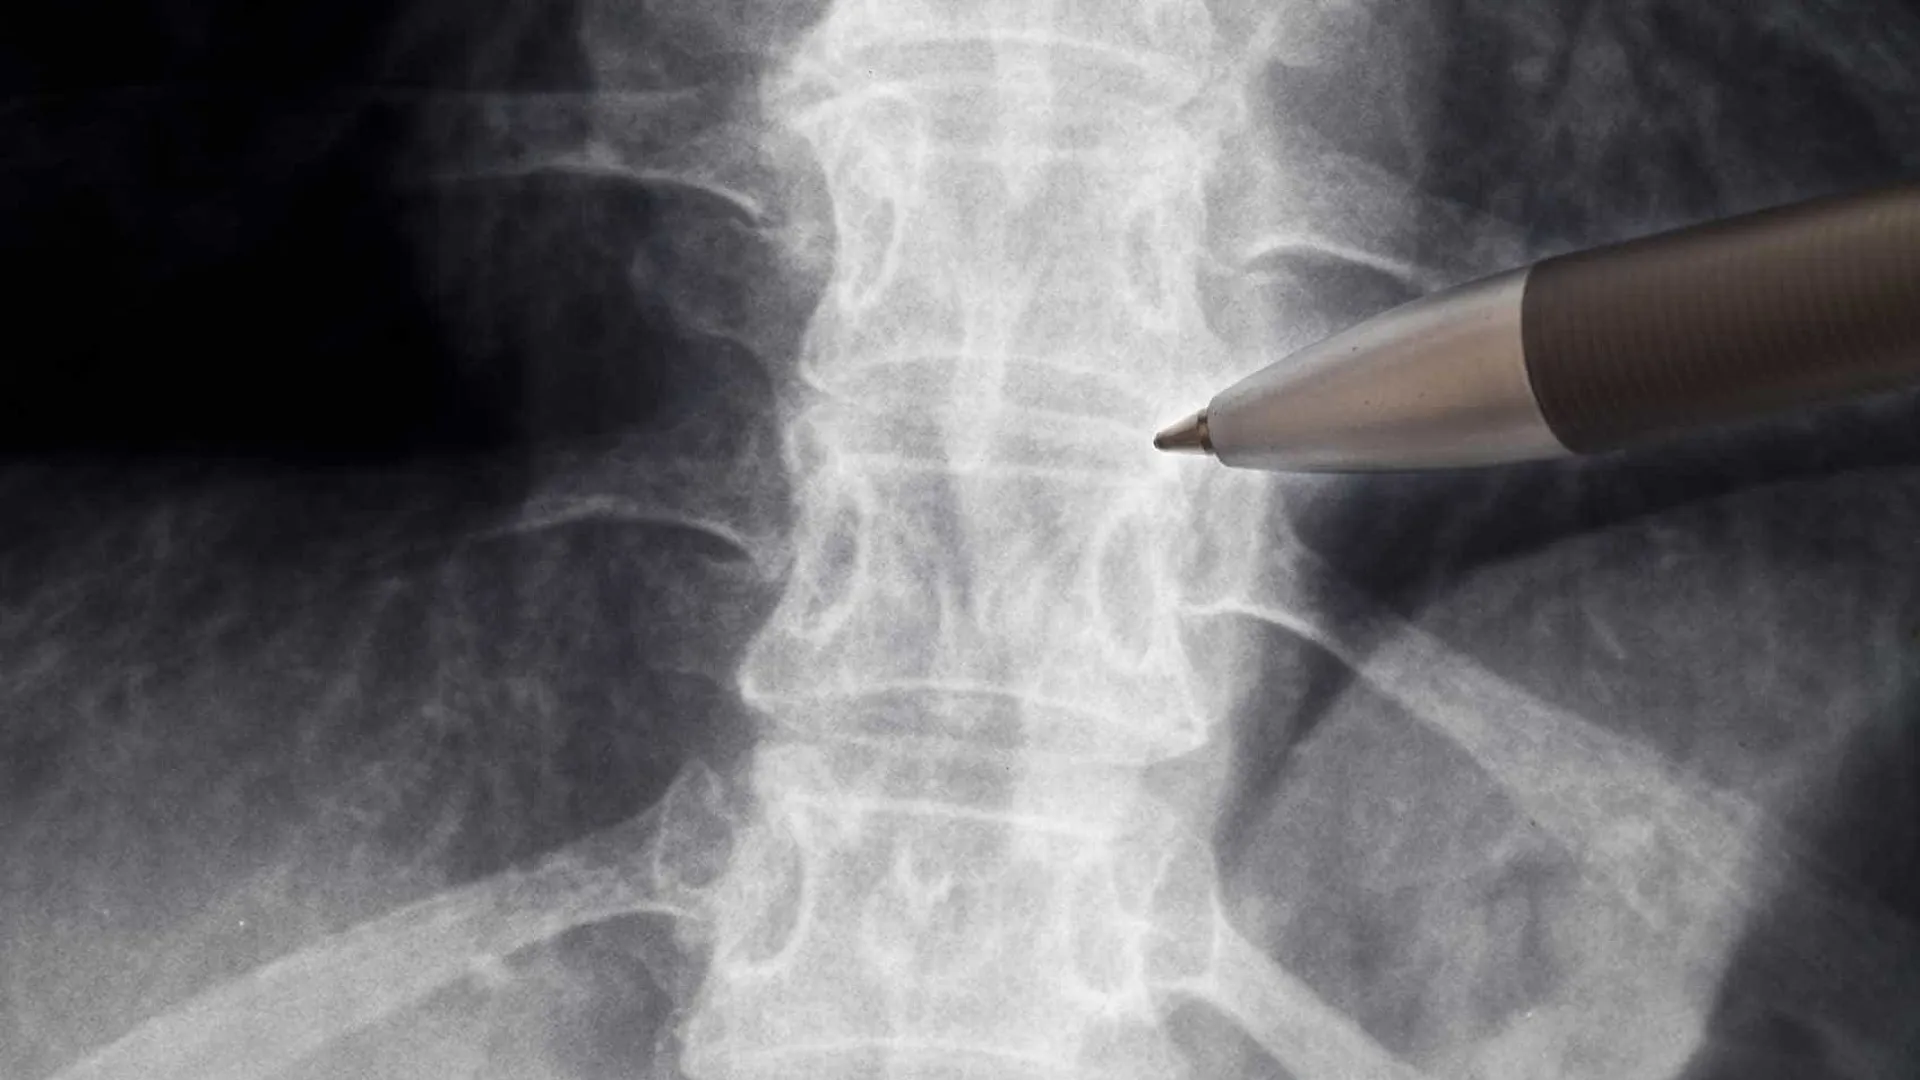

Anvisa libera estudo com medicamento para lesões na medula espinhal

A Agência Nacional de Vigilância Sanitária (Anvisa) autorizou o início do estudo clínico para avaliar a segurança do uso do medicamento polilaminin…